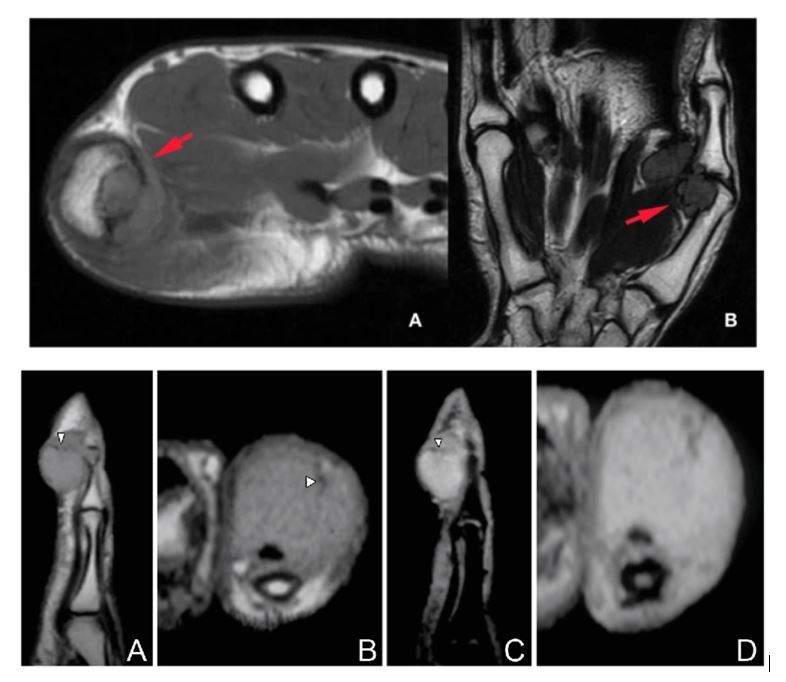

A swelling is found on volar aspect of the thumb. MRI is performed and as attached.

1. What is the likely diagnosis?

2. What other DDXs?

3. How may this patient present clinically?

4. How can you confirm this DX?

5. How will you treat this conditon?

1. GCT of tendon sheath of thumb flexor tendon

2. Differential diagnosis

If with MRI - fibroma/fibrosarcoma/glomangioma

If no MRI- ganglion cyst, epidermal inclusion cyst

1. Painful, firm, nodular mass

Pain worsens with activity

Moves with passive flexion of flexor tendons - part of tendon sheath

No transillumination

May affect ROM of adjacent joint

1. Confirmation of DX

USG

• demonstrate relation of lesion to adjacent tendon

• homogenous hypoechoic lesion, may have some internal vascularity & heterogeneity

MRI

• focal mass with decreased signal intensity on both T1 and T2 weighted images.

• can be homogenous or hetergenous

5. Marginal excision

Have to inform patient rate of recurrence 5-50% especially it

• tumour is deep within the joints and deep to volar plate

• if tendon is also involved